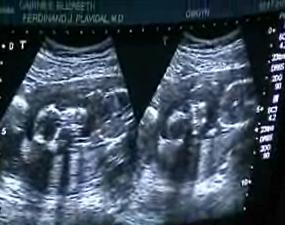

Ultrasound video short version - 4 minutes - 7MB

Ultrasound video full version - 15 minutes - 19MB